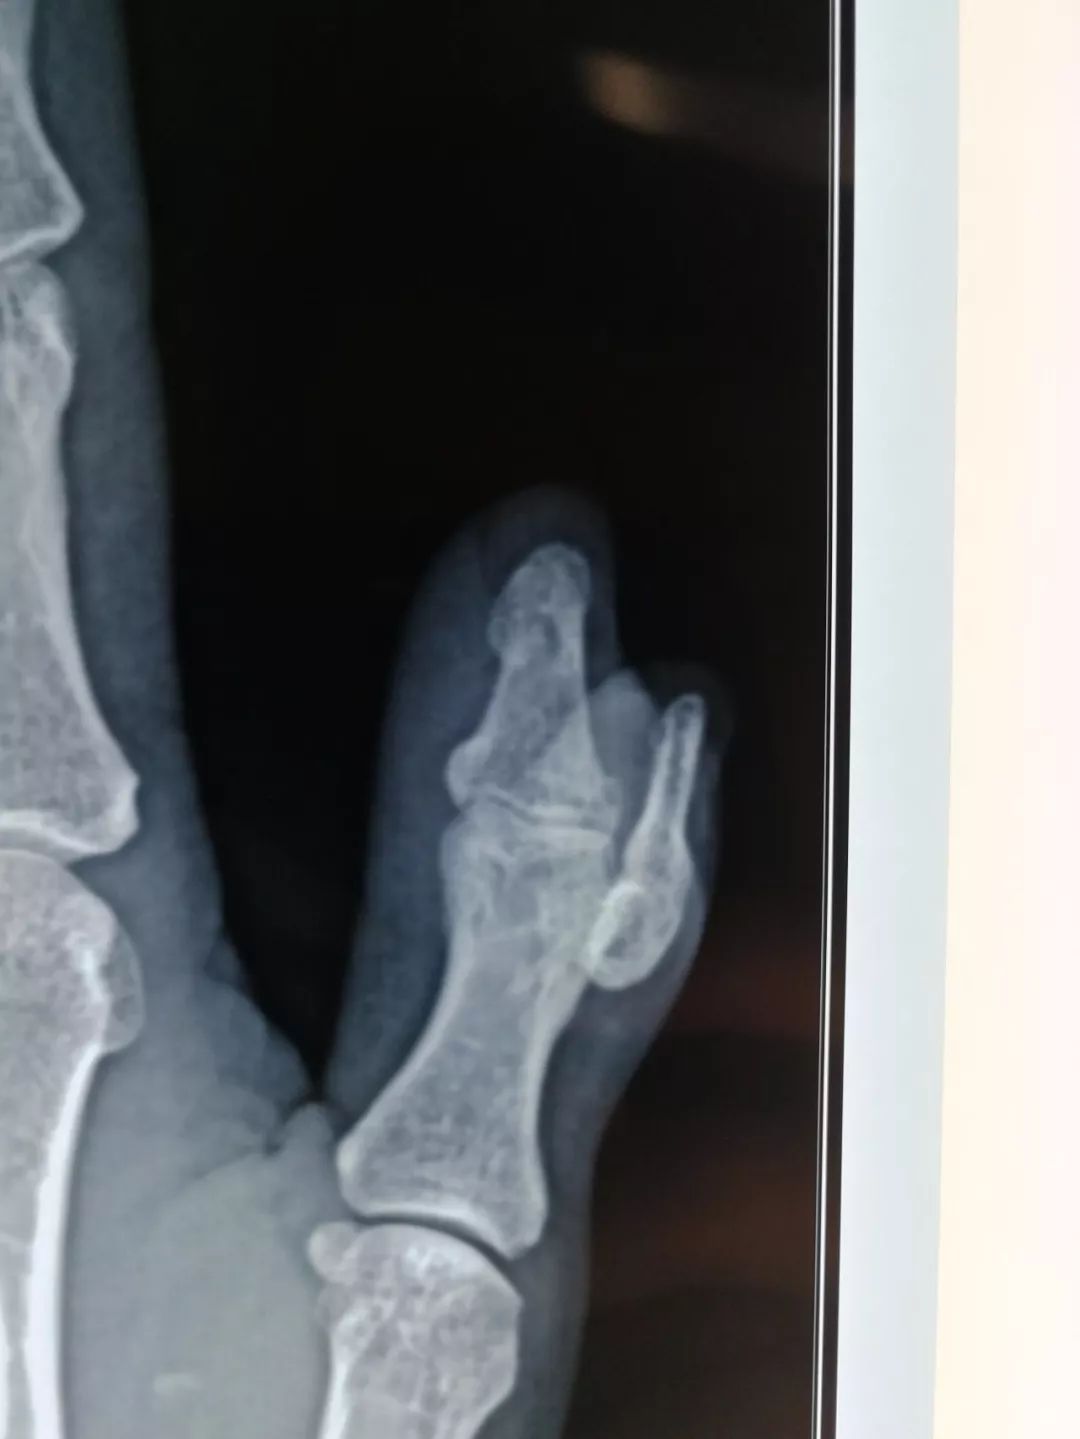

△杨大爷右手的x光片

黄女士的右手x片